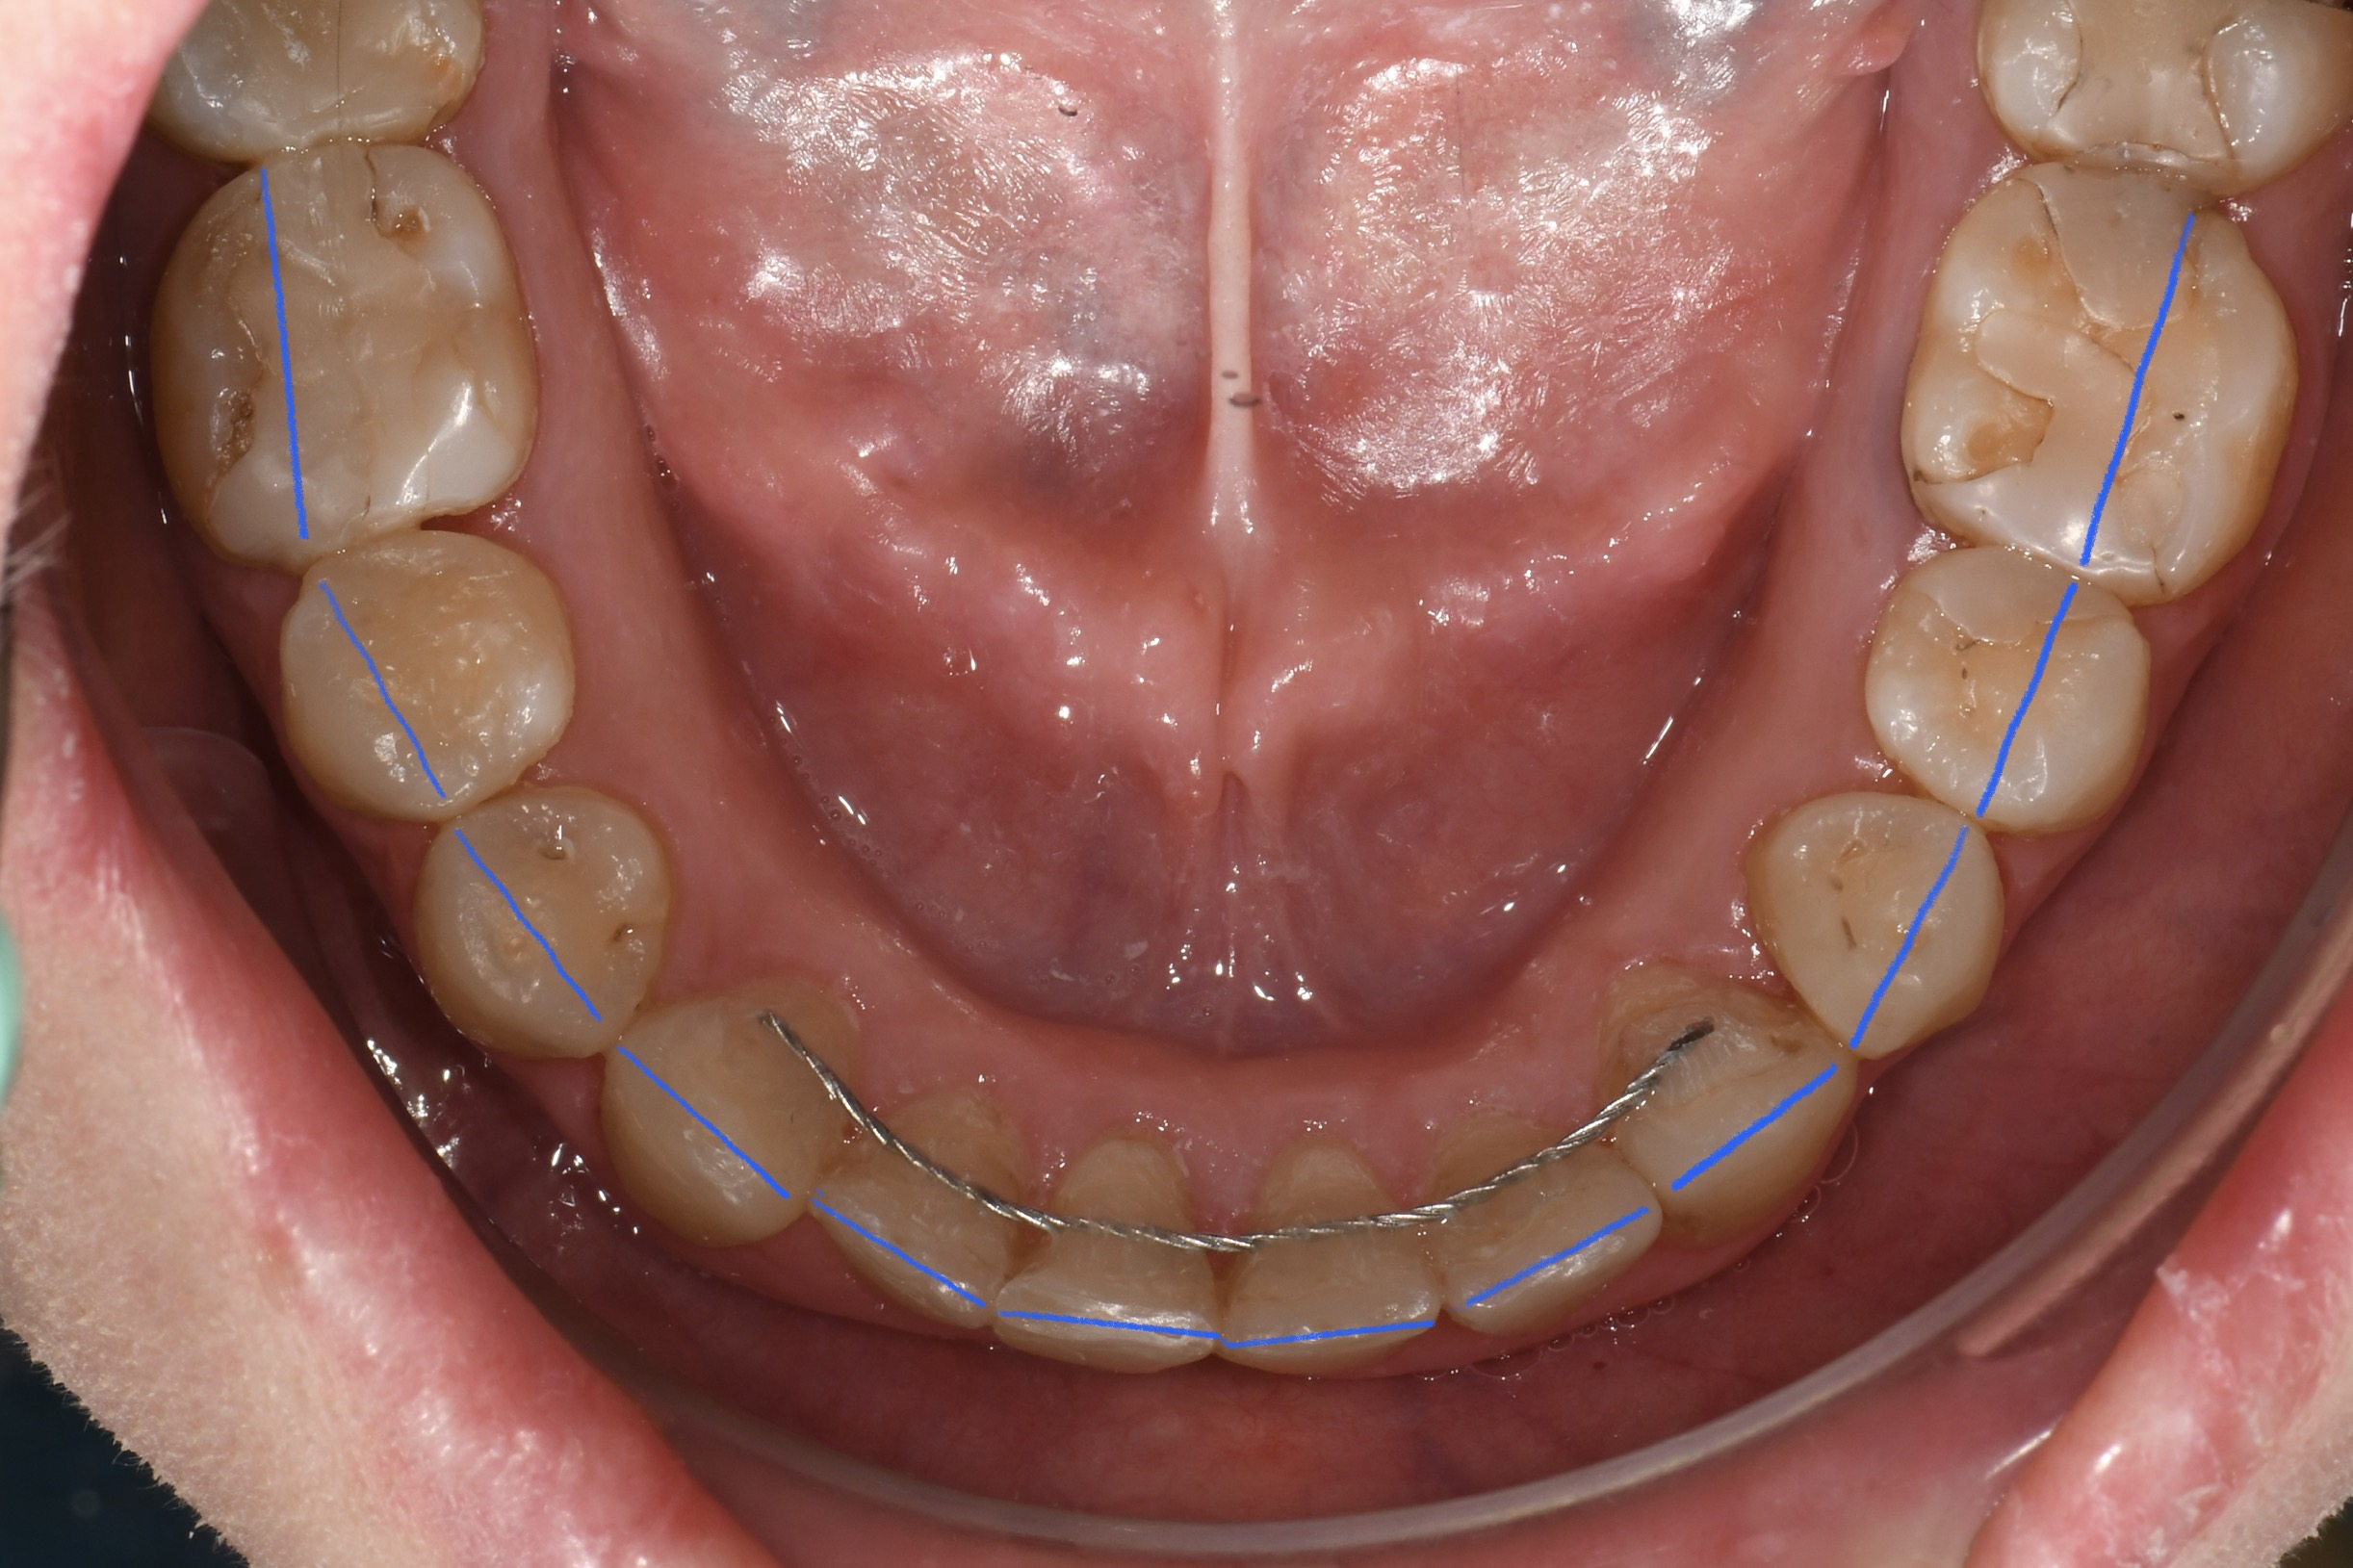

Az elmúlt évekből rengeteg szakmai referenciát tudnánk bemutatni, amelyek különböző fogszabályozási problémákat oldottak meg. Válogatva a több száz esetből, ezen az oldalon olyan képeket, információkat igyekeztünk bemutatni, amelyeknek a segítségével a jövőbeni pácienseinknek azt tudjuk üzenni: A Te fogsorod is lehet gyönyörű!

(Képeket a Pácienseink külön írásos beleegyezésével mutatjuk be!)